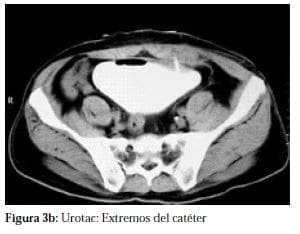

Una radiografía simple de abdomen (figura 1), cistografía (figura 2), las cuales mostraban la porción distal del catéter en la pelvis menor, así mismo se realizó urotac (figura 3a y b) que confirma la presencia del catéter en la vejiga.

Al paciente se le practica uretrocistoscopia que confirmo la presencia del catéter en vejiga (figuras 4a y b), bajo anestesia general se practica exploración abdominal, descartando presencia de catéter en esta cavidad, se realiza exploración del espacio prevesical evidenciando la presencia de catéter que se introducía a la vejiga por la parte media de la pared lateral izquierda (figura 5a).

La uropatia neurogénica que conlleva a vejigas atónicas o hipotónicas se asocia con diabetes de larga evolución. La placa de abdomen simple se puede considerar diagnostica, tanto en la posición antero posterior como oblicua, la porción distal del catéter entorchado, se encuentra en posición suprapúbica y sobre la silueta vesical y muy por debajo del repliegue peritoneal inferior, hallazgos que se confirmaron mediante Urotac y uretrocistoscopia, previos la corrección quirúrgica y reacomodación del catéter.